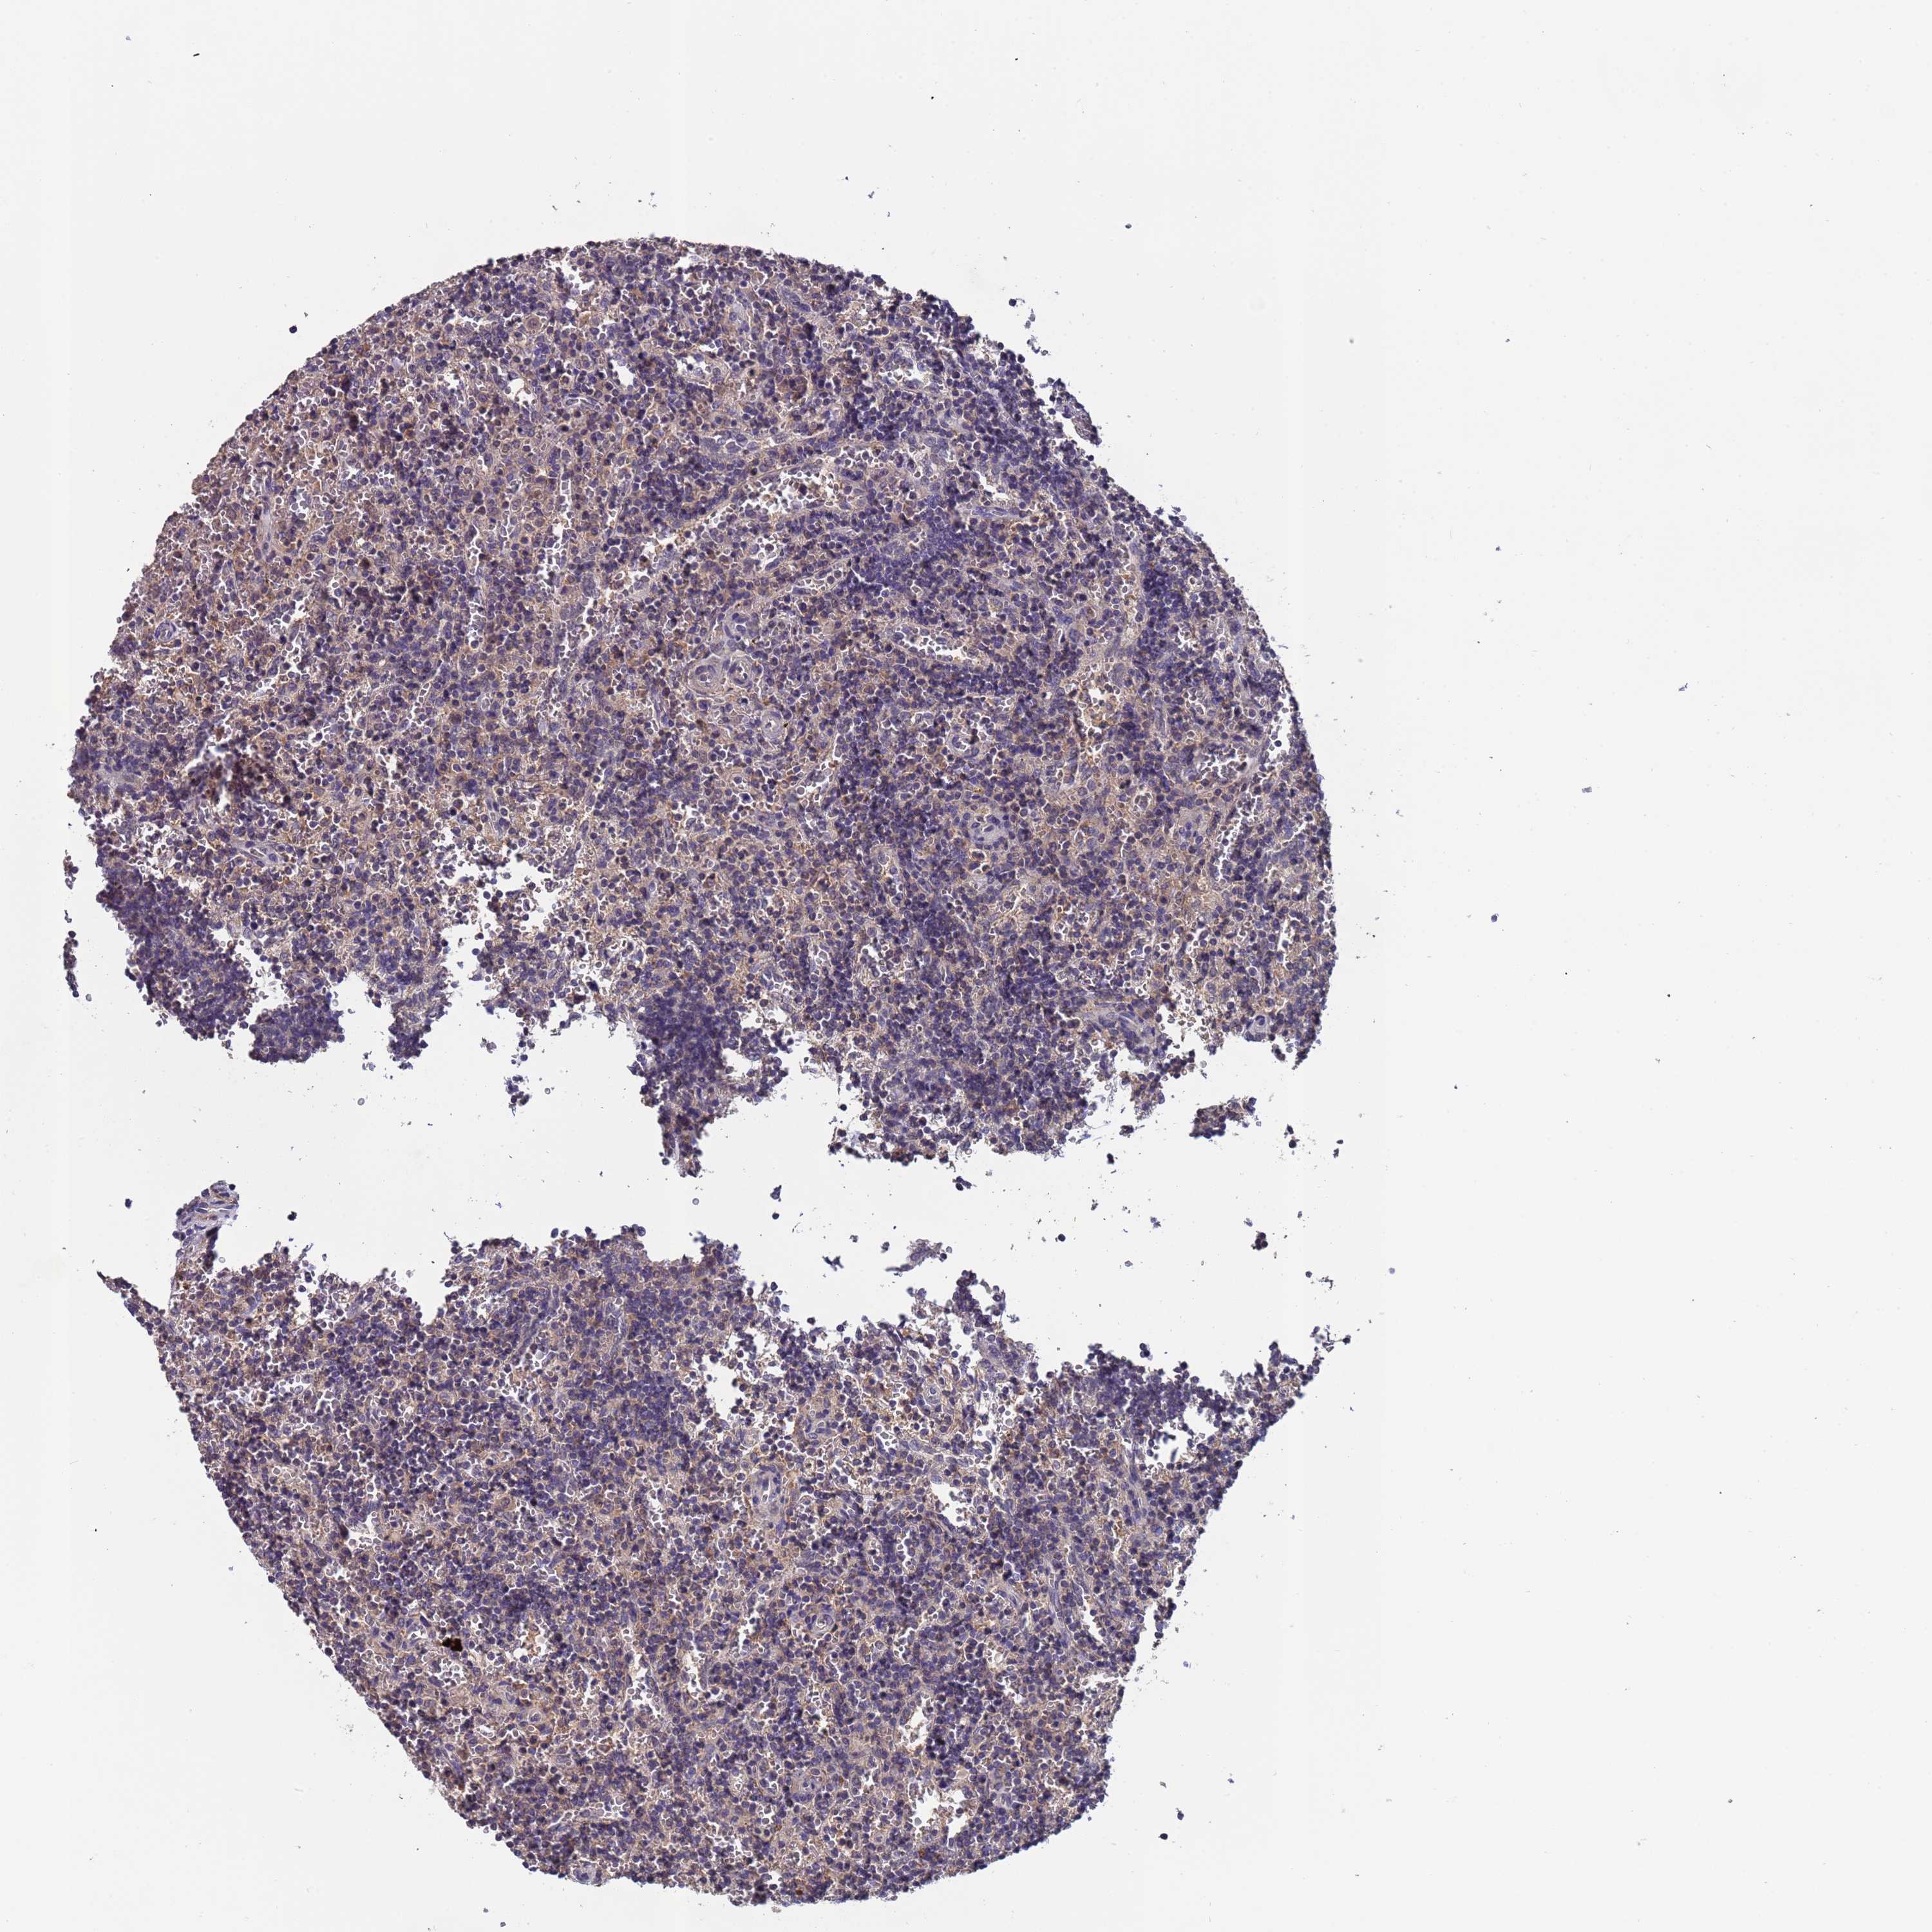

CANCER LYMPHOMA Show tissue menu

LYMPHOMA - Protein expressioni

A mouse-over function shows sample information and annotation data. Click on an image to view it in a full screen mode. Samples can be filtered based on level of antibody staining by selecting one or several of the following categories: high, medium, low and not detected. The assay and annotation is described here.

Each image is clickable and will lead to virtual microscopy that enables deeper exploration of all samples and also displays staining intensity scores, fraction scores and subcellular localization as well as patient and tissue information for each sample.

Antibody HPA018237

Hodgkin's disease, NOS

Malignant lymphoma, non-Hodgkin's type, High grade

Malignant lymphoma, non-Hodgkin's type, Low grade